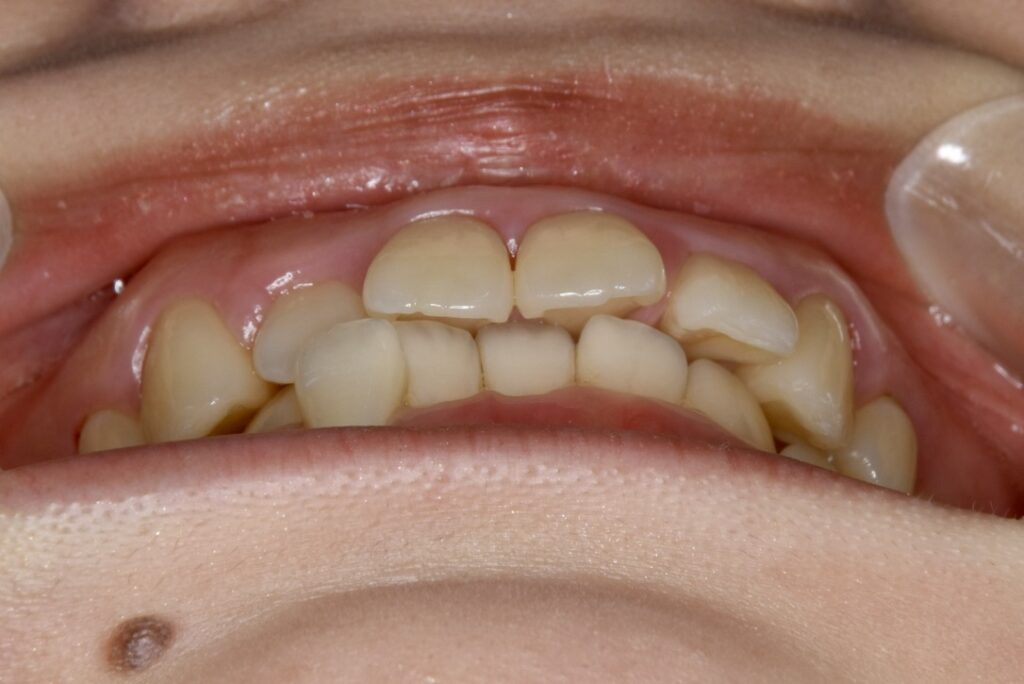

21歳 女性 治療期間:1年1ヶ月

叢生(ガタガタ)

マウスピース矯正装置(インビザライン)

BEFORE

周りの人の歯並びが綺麗で自分の歯並びを治したくなってきた。

叢生

上下とも歯並びの横幅を広げながら、でこぼこを解消しました。